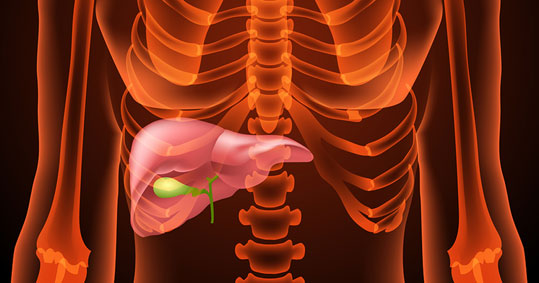

Είναι η βαρεία οξεία μικροβιακή φλεγμονή της χοληδόχου κύστης. Οφείλεται σε παρατεταμένη απόφραξη του κυστικού πόρου από λίθο (πέτρα) που βρίσκεται μέσα στην χοληδόχο κύστη.

• Πόνος. Το κυρίαρχο σύμπτωμα είναι ο πόνος, στο δεξιό άνω πλάγιο της κοιλιάς (δεξιό υποχόνδριο) και το επιγάστριο με αντανάκλαση στην πλάτη.

Όπως αναφέρει το saritzoglou.com, η πάθηση συνοδεύεται από υψηλό πυρετό και ψηλαφητή επώδυνη μάζα στο δεξιό υποχόνδριο, στην ανατομική θέση της χοληδόχου κύστης.